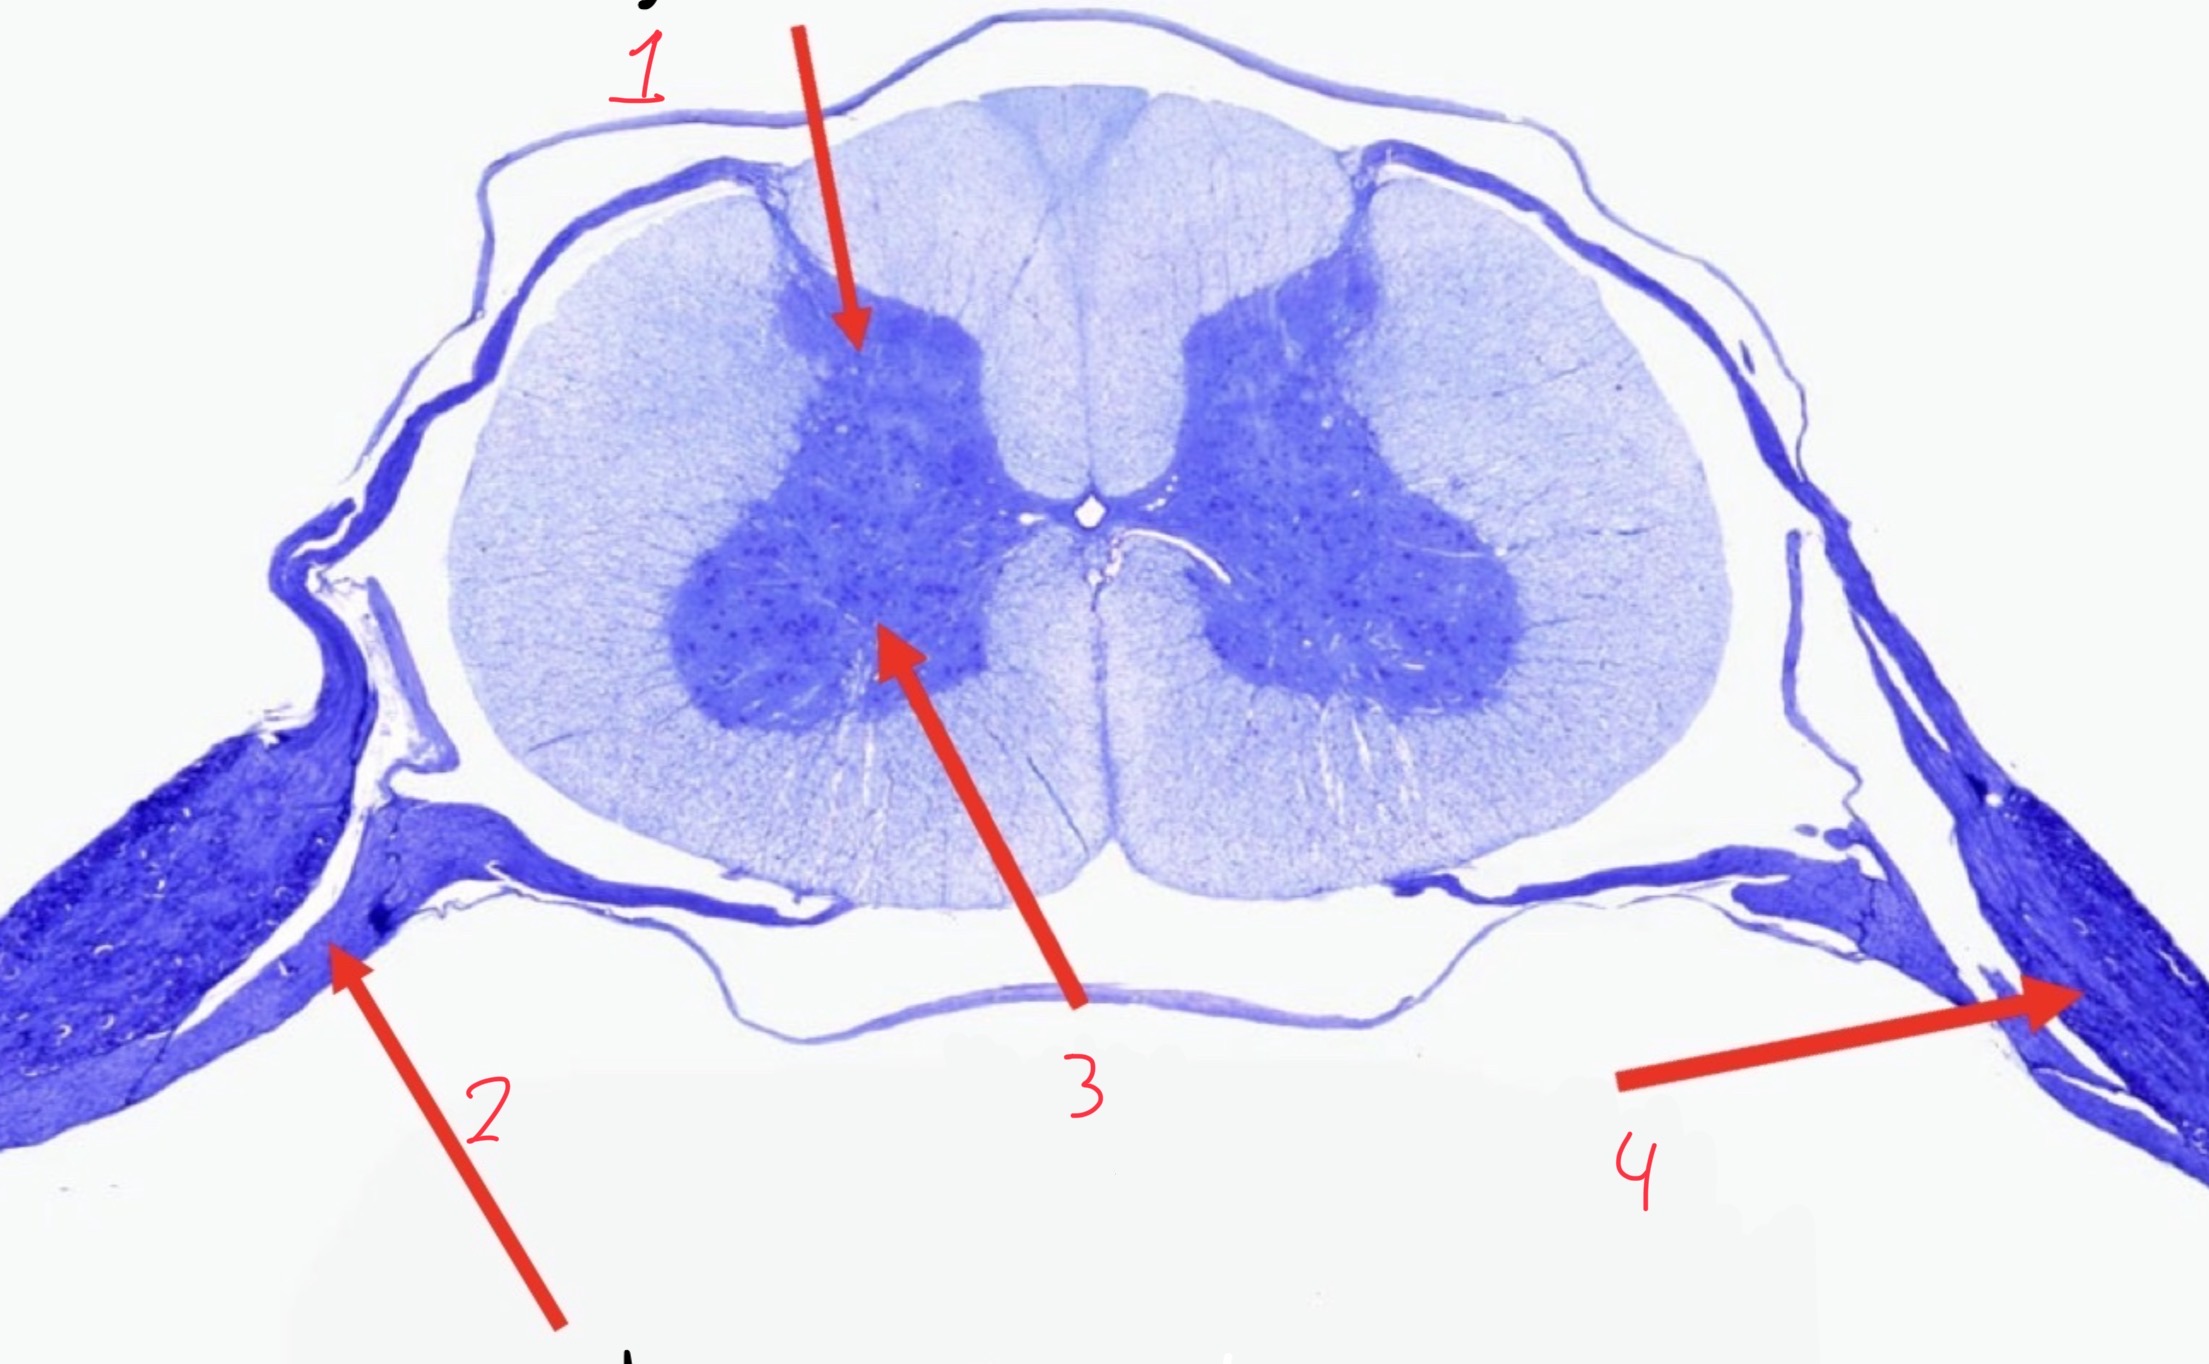

1

Dorsal horn

2

ventral root

3

Ventral horn

4

Dorsal root ganglion